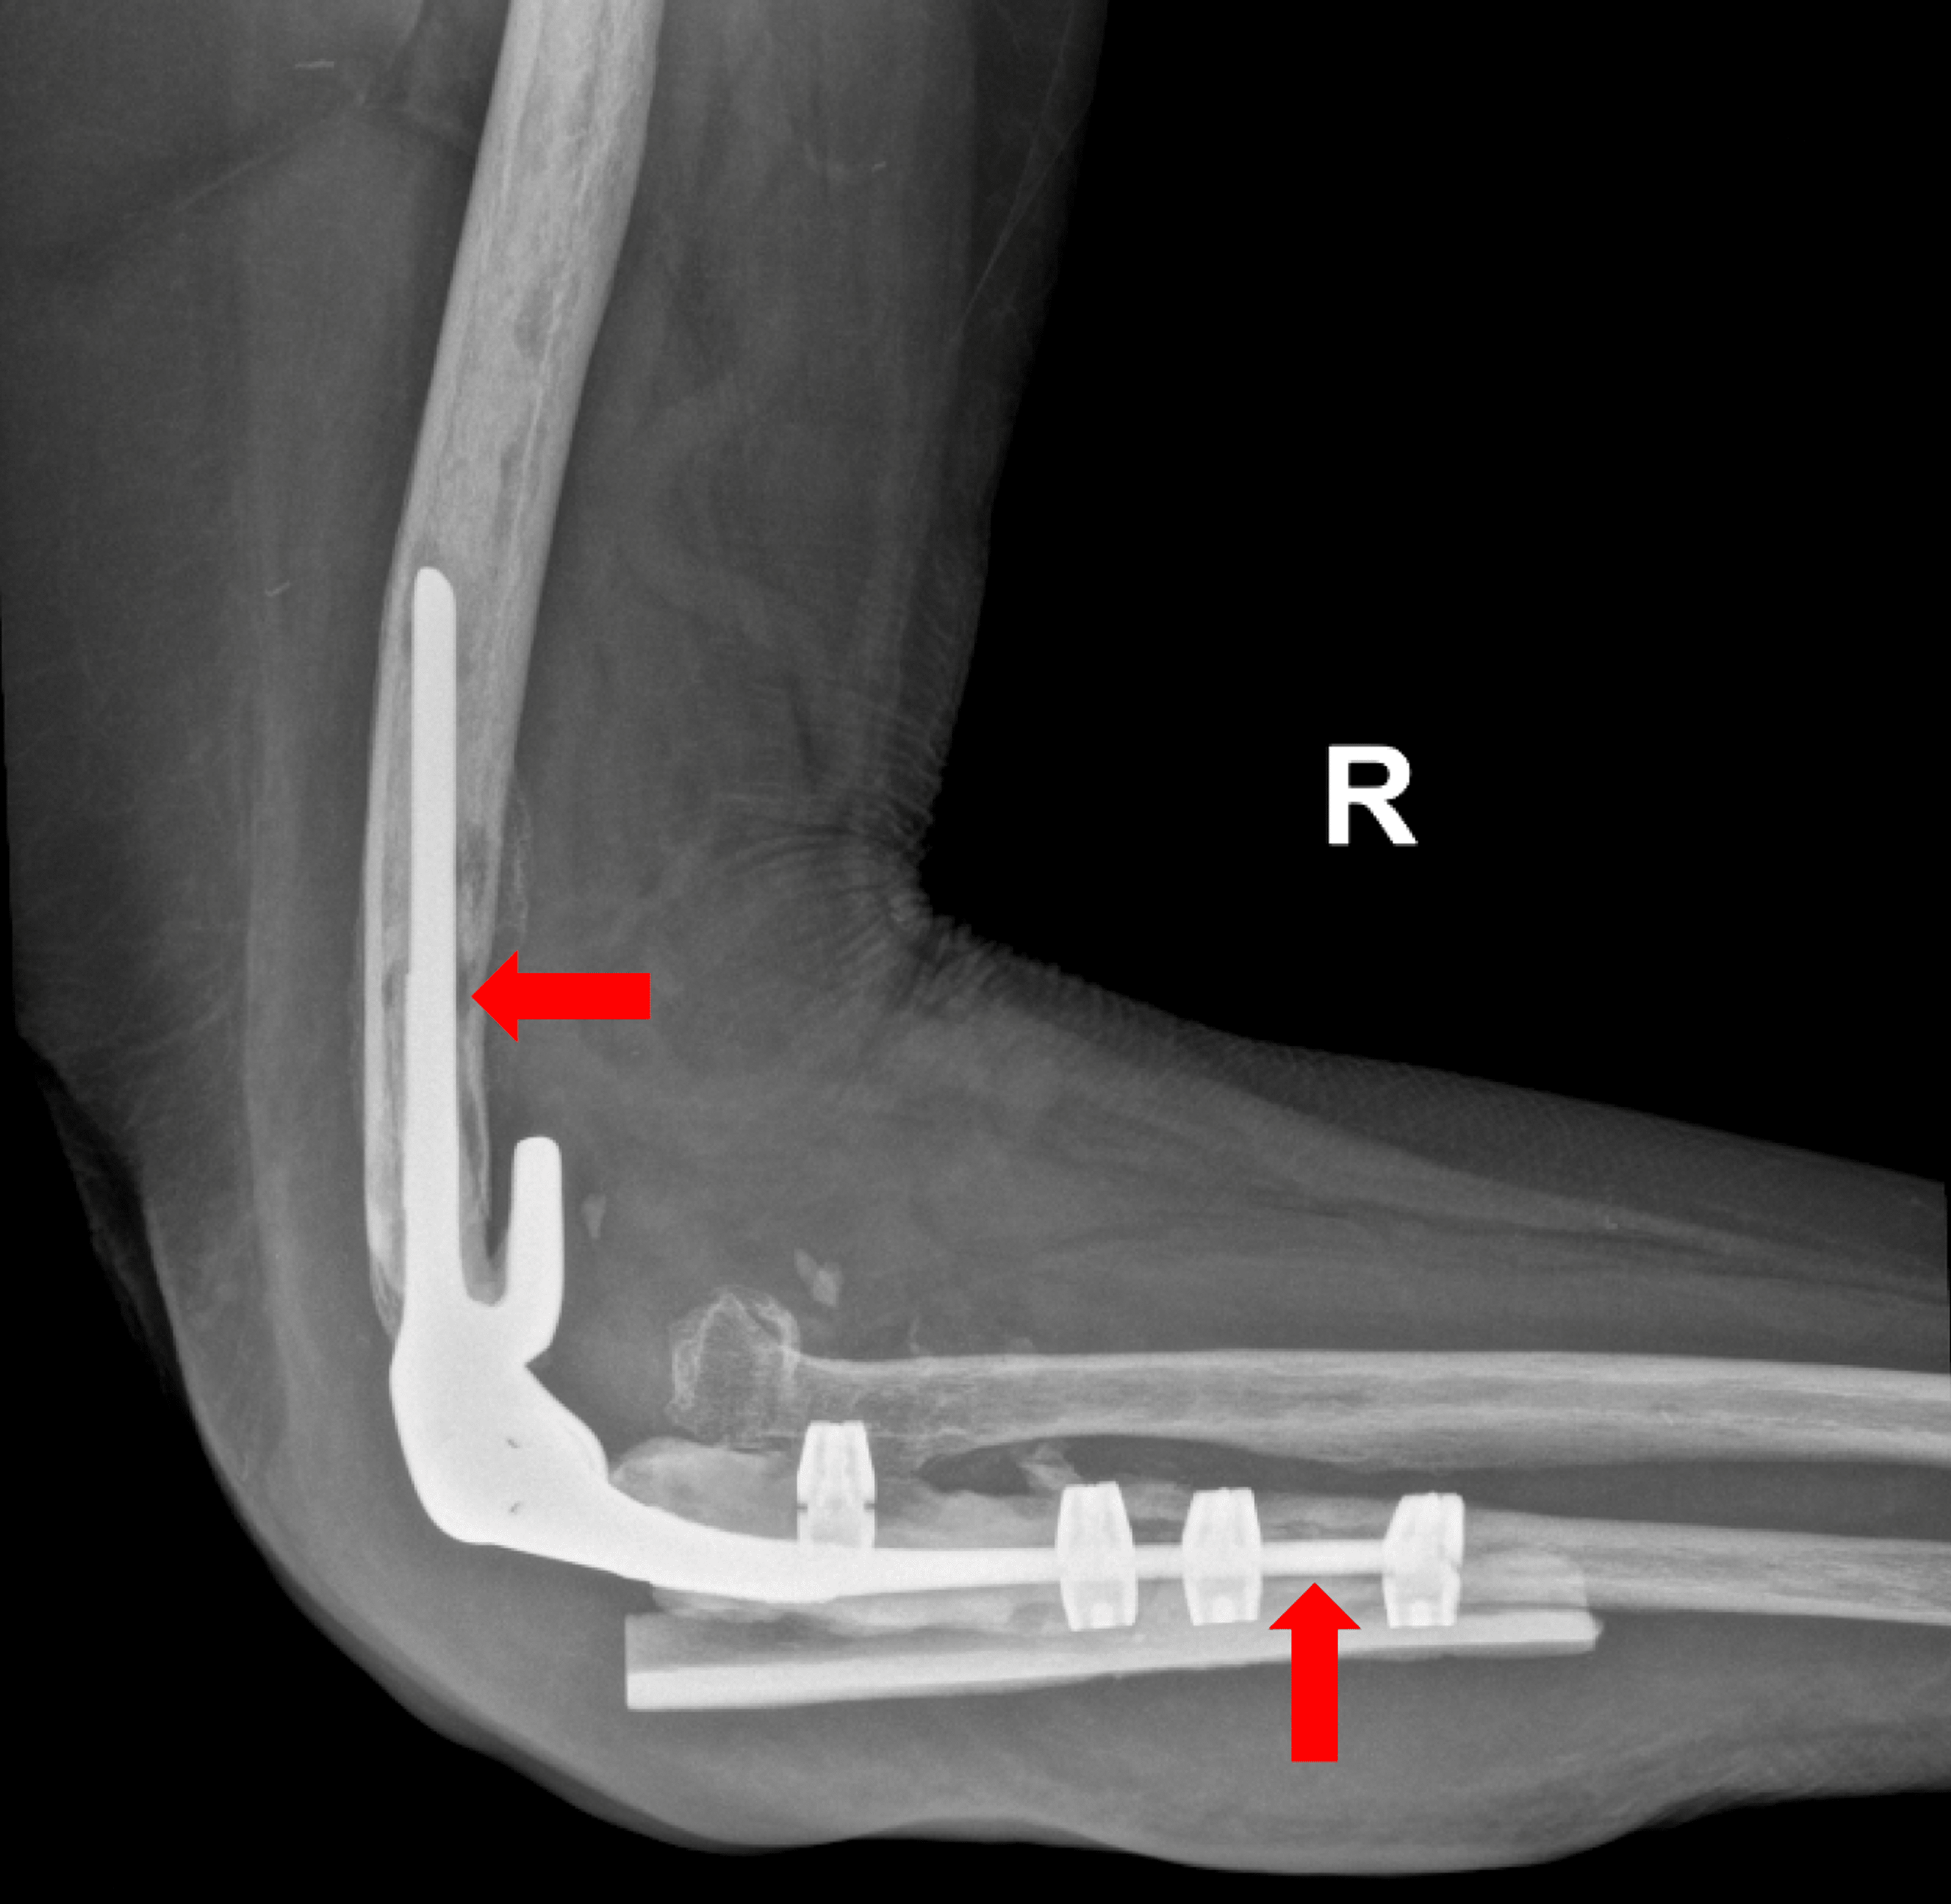

Cureus Intercalary Elbow Resection and Arthrodesis for Giant Cell Elbow Joint Surgery In total elbow replacement surgery, the damaged parts of the humerus and ulna are replaced with artificial components. The stems fit inside the hollow part of the bone called the canal. Elbow replacement surgery (sometimes referred to as total elbow arthroplasty) is an operation that surgeons use. If a disease such as rheumatoid arthritis or an injury has harmed your. Elbow Joint Surgery.

Challenging elbow revisions total elbow arthroplasty with massive bone Elbow Joint Surgery The artificial elbow joint is made up of a metal and plastic hinge with two metal stems. An elbow replacement removes a damaged elbow joint and replaces it with an artificial joint called a prosthesis. Elbow replacement surgery (sometimes referred to as total elbow arthroplasty) is an operation that surgeons use. If a disease such as rheumatoid arthritis or an. Elbow Joint Surgery.